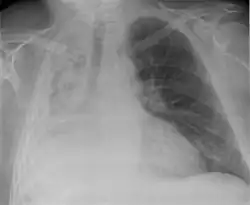

Post-operative changes

Chest x-ray showing an individual who had their right lung removed with fluid accumulating in the operated side.

A pneumonectomy is a surgical procedure in which an entire lung is removed. A common reason for performing this procedure is for lung cancer originating in the lung itself.[19] This leads to a mediastinal shift towards the empty side of the thorax. Notably, patients can experience post pneumonectomy syndrome due to a severe mediastinal shift. This presents as difficulty breathing due to a shift of airways and rotation of the heart and great vessels. On x-ray, white out of the operated side and hyperinflation of the remaining lung is often observed.[20]